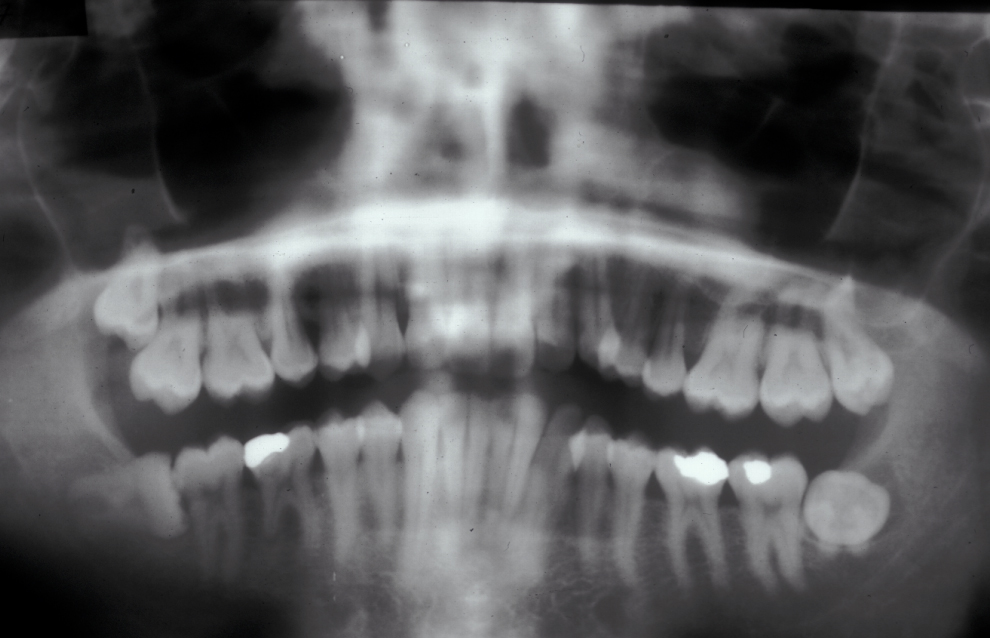

These points help to determine whether the tooth can be simply elevated or will need a surgical approach. A series of radiographs depicted in Figure 4 to Figure 8 illustrate these points further.

Having established that the wisdom tooth needs to be removed, other points in the assessment include:

- tooth position (vertical, mesioangular, distoangular, horizontal or across the arch).

- depth and degree of impaction;

- obstruction to eruption (what is the tooth impacted against?);

- root morphology (the curvature of the roots controls the path of withdrawal);

- relationship to the inferior dental nerve canal;

- associated pathology (for example, cysts);

- bone density;

- status of second molar tooth (in selected cases where this tooth has a poor prognosis it may be better to extract it and leave the third molar).